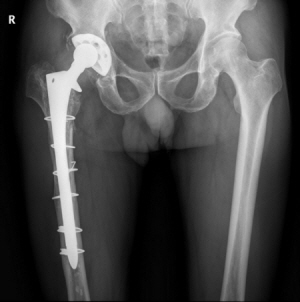

‘프록시마’를 이용해 시술한 고관절 엑스레이 사진 |

기존 인공관절을 이용해 시술한 고관절 엑스레이 사진 |

프록시마는 기존 인공관절보다 크기를 줄이는 대신 인체의 하중을 받는 대퇴부의 끝 부분에만 골 접착제 없이 삽입하는 인체공학적 디자인으로 설계돼 정상적인 뼈의 힘을 받는 부분에만 응력이 발생하도록 해줌으로써 뼈를 원래대로 보존해줘 오랫동안 사용할 수 있다. 기존에 일반적으로 사용되던 모양이 긴 엉덩이 인공관절은 고정력을 높이기 위해 길이가 긴 아랫 부분을 인체의 뼈에 깊숙이 삽입하므로 수술 후 대퇴부에 통증이 올 수 있고, 오랫동안 사용하다 보면 주위 뼈 조직이 약해질 수 있어 재수술을 받아야 하는 단점이 있었다.

프록시마는 세라믹 델타 소재를 사용해 강도를 2배로 늘리고 마모도는 기존 소재 대비 1/5000로 대폭 줄여 인체에 미치는 부작용을 최소화했다. 또한 관절을 연결하는 볼의 크기를 36mm로 크게 해 탈구를 예방해준다. 기존의 대퇴골두 인공관절은 작은 크기의 볼을 사용해 탈구가 일어나는 일이 있곤 했다.